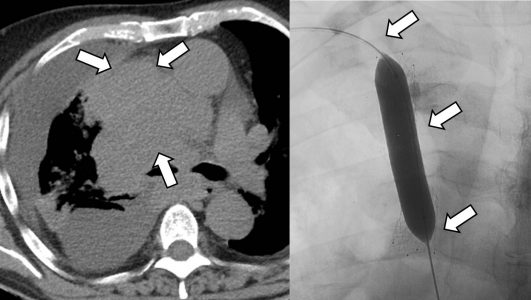

Σε έναν δεύτερο πυλώνα ογκολογικής θεραπείας η Επεμβατική Ακτινολογία μπορεί να εφαρμόσει τοπικοπεριοχική θεραπεία καταστροφής των καρκινικών κυττάρων με τεχνικές είτε διαδερμικής κατάλυσης (Ablation) είτε διαδερμικού ενδαγγειακού χημειοεμβολισμού (TACE). Στην περίπτωση της κατάλυσης μπορεί να εφαρμοστεί σε καρκινώματα του ήπατος, του νεφρού, των οστών και των όγκων μαλακών μορίων και υπό προυποθέσεις στον πνεύμονα. Παθοφυσιολογικά βασίζεται στην τοπική καταστροφή των καρκινικών κυττάρων με τη δημιουργία ιδιαίτερα υψηλών θερμοκρασιών νέκρωσης εντός του όγκου. Αυτό επιτυγχάνεται με τοποθέτηση ειδικών βελονών-ηλεκτροδίων εντός του όγκου υπό ακτινολογική καθοδήγηση. Τα ηλεκτρόδια αυτά παράγουν υψηλή θερμοκρασία είτε με τη βοήθεια ραδιοσυχνοτήτων (RF ablation) είτε με τη βοήθεια μικροκυμάτων (MW ablation) και προκαλούν πηκτική νέκρωση των καρκινικών κυττάρων χωρίς να επηρεάζουν τα φυσιολογικά κύτταρα.

Ο χημειοεμβολισμός είναι μια επικουρική μέθοδος τοπικής θεραπείας για πρωτοπαθή και δευτεροπαθή νεοπλάσματα του ήπατος. Στόχος του επεμβατικού ακτινολόγου είναι η τοπική έγχυση χημειοθεραπευτικού σε κλάδους της ηπατικής αρτηρίας, ώστε να επιτευχθούν υψηλές συγκεντρώσεις τοπικά στην ηπατική εξεργασία χωρίς να προκαλούνται συστηματικές επιπλοκές τοξικότητας του χημειοθεραπευτικού. Επιπλέον, προκαλείται τοπική ισχαιμία-νέκρωση στην περιοχή του όγκου από τα εμβολικά υλικά-μικροσφαιρίδια εμβολισμού, χωρίς να επηρεάζεται το φυσιολογικό ηπατικό παρέγχυμα.